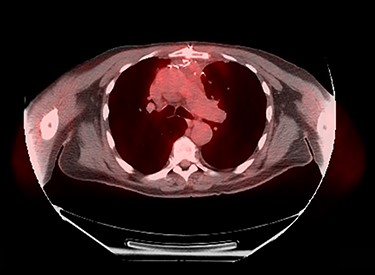

Sixty-three-year-old male was with the history of diabetes and hypertension who presented with 2 days of new onset, intermittent and non-pleuritic left-sided chest pain, with a few months of new onset exertional dyspnea. Chest X-ray showed a convex shaped mass at the left hilum. Chest CT angiography revealed a 5.6 × 7.1 × 5.4 cm hypodense mass in the anterior mediastinum involving the adjacent anterior medial left upper lobe, and adjacent mildly enlarged aorticopulmonary window lymph nodes (Fig. 1). PET scan demonstrated a hypermetabolic anterior mediastinal mass adjacent to medial left upper lobe highly suggestive of malignancy (Fig. 2). Ultrasound-guided core needle biopsy showed nests of small cells with peripheral palisading and focal abrupt transition to squamous cell, consistent with basaloid carcinoma of thymic gland. Immunostainings of the tumor cells were positive for cytokeratin AE1/AE3, cytokeratin CK904, p63 and p40.

Chest CT angiography revealed a 5.6 × 7.1 × 5.4 cm hypodense mass in the anterior mediastinum involving the adjacent anterior medial left upper lobe.